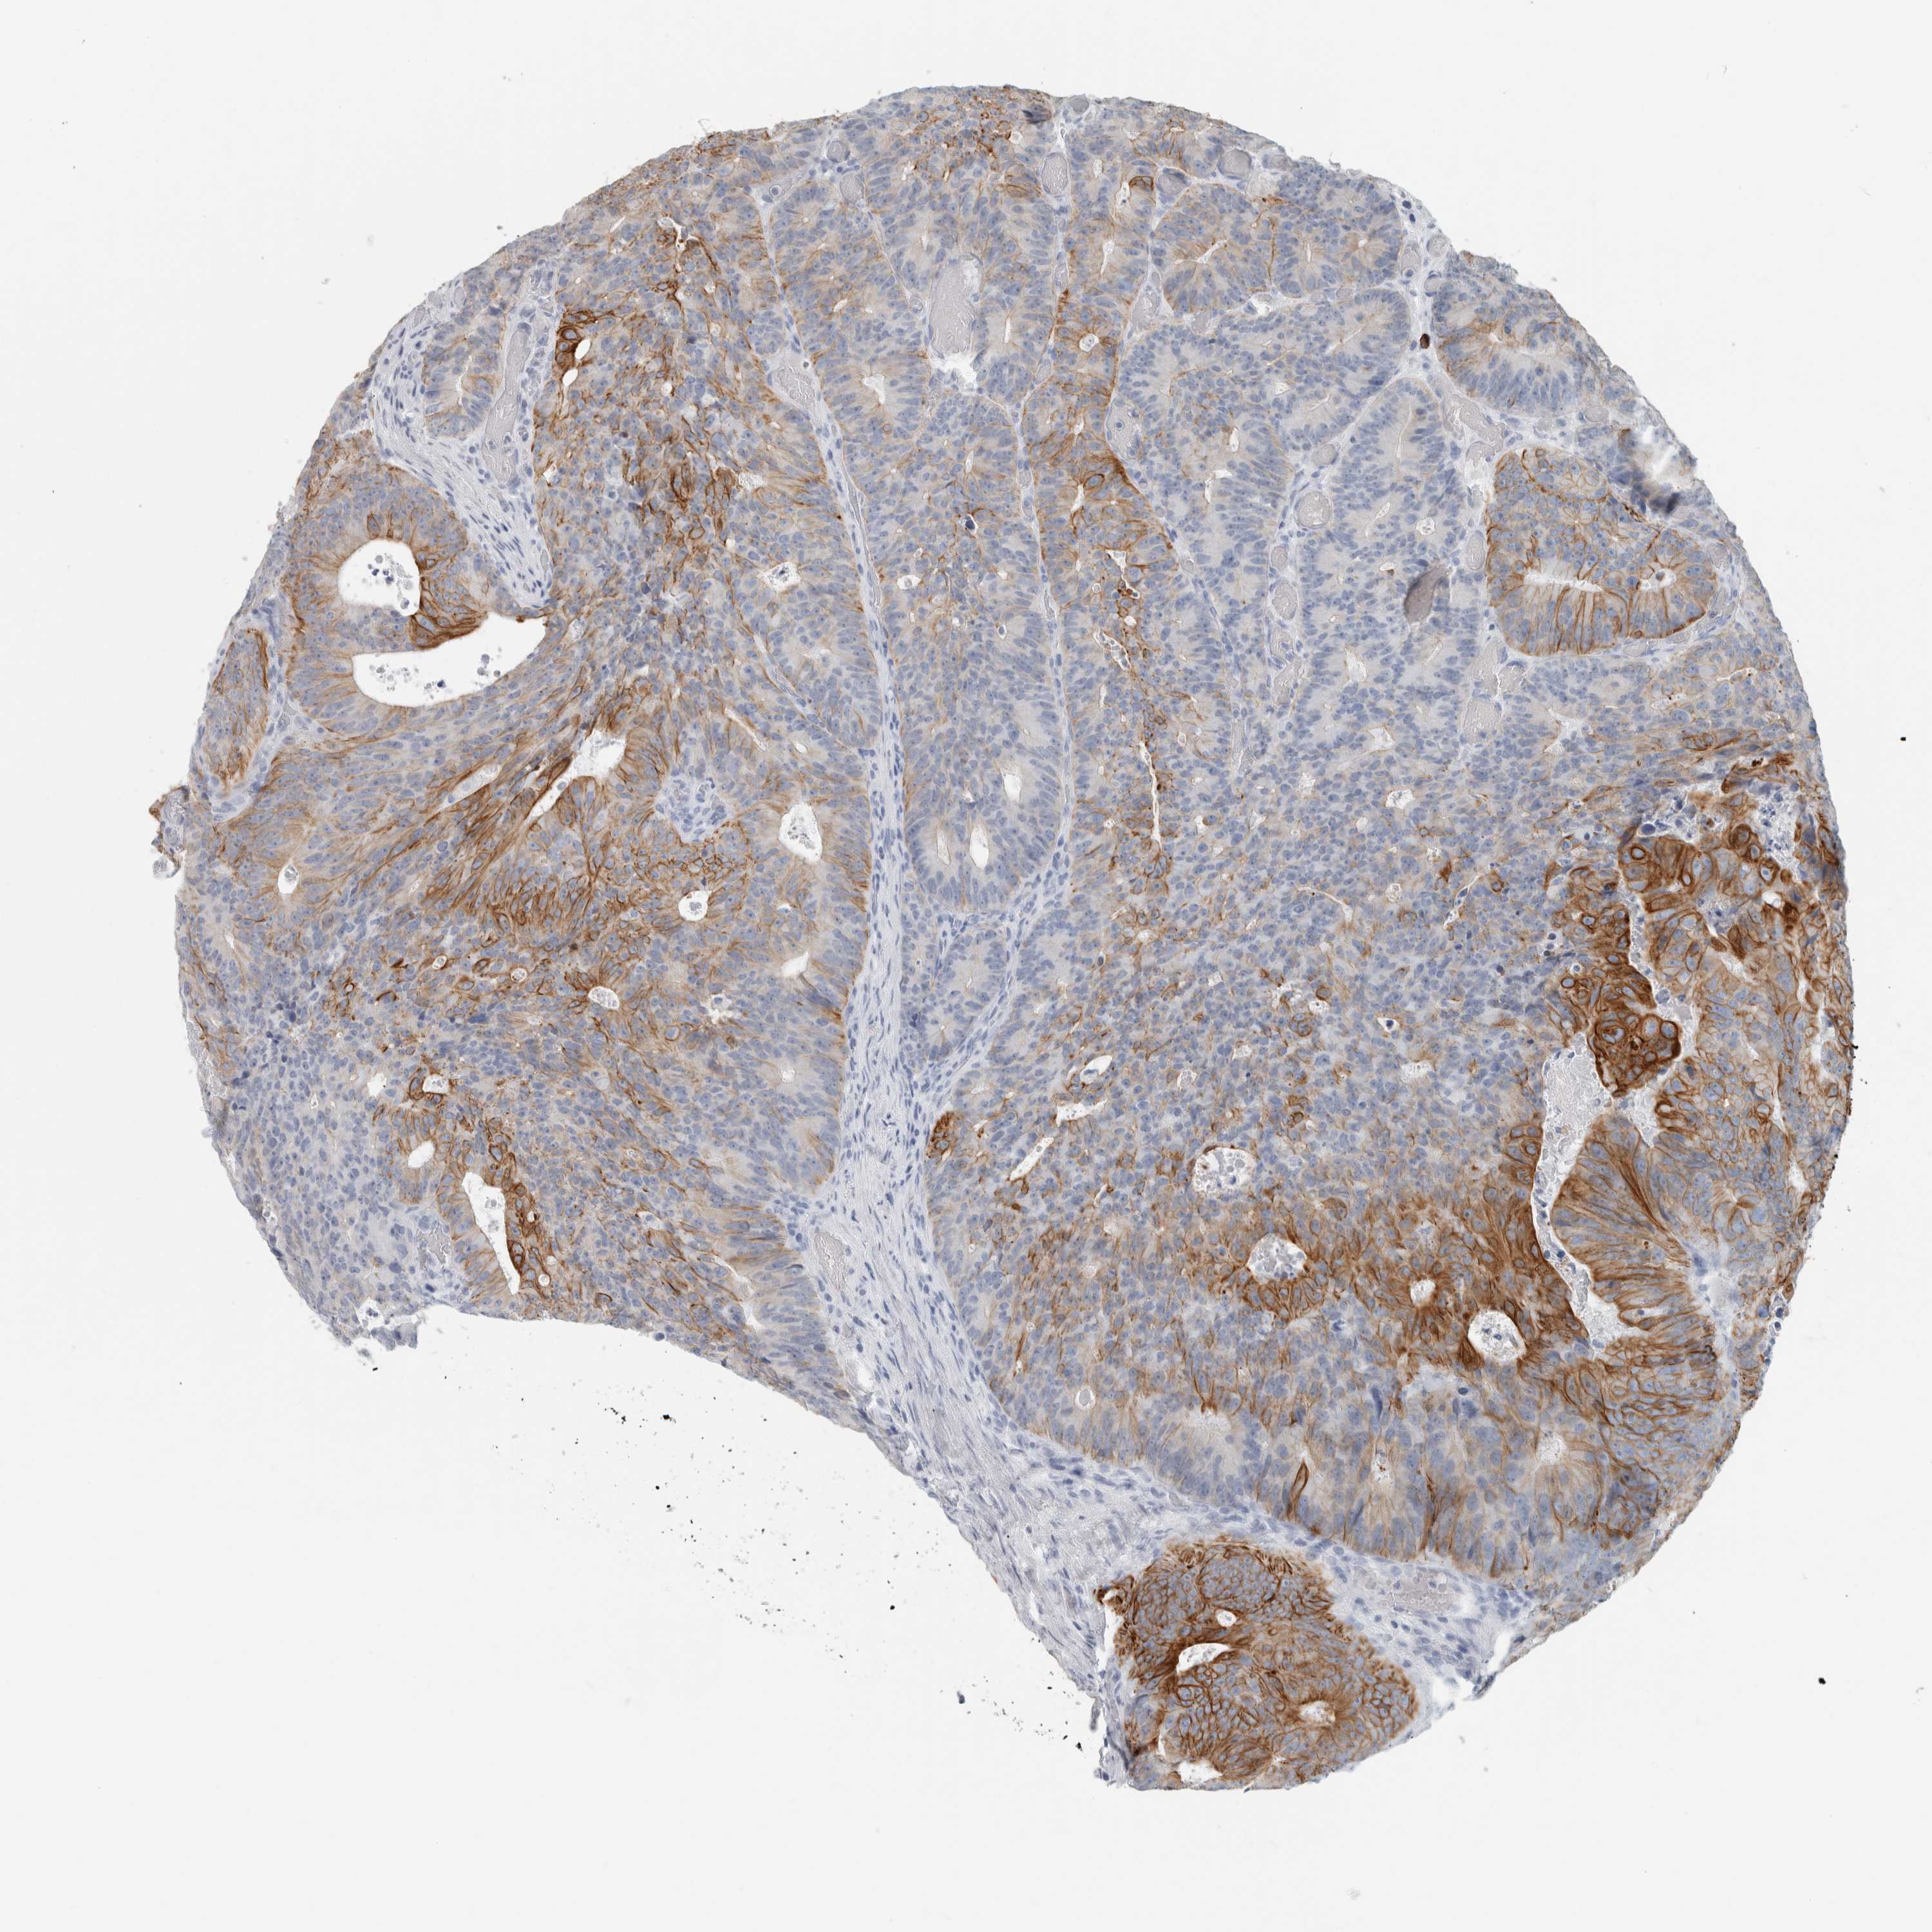

CANCER COLORECTAL CANCER Show tissue menu

Colorectal cancer

Human cancer

Colon adenocarcinoma